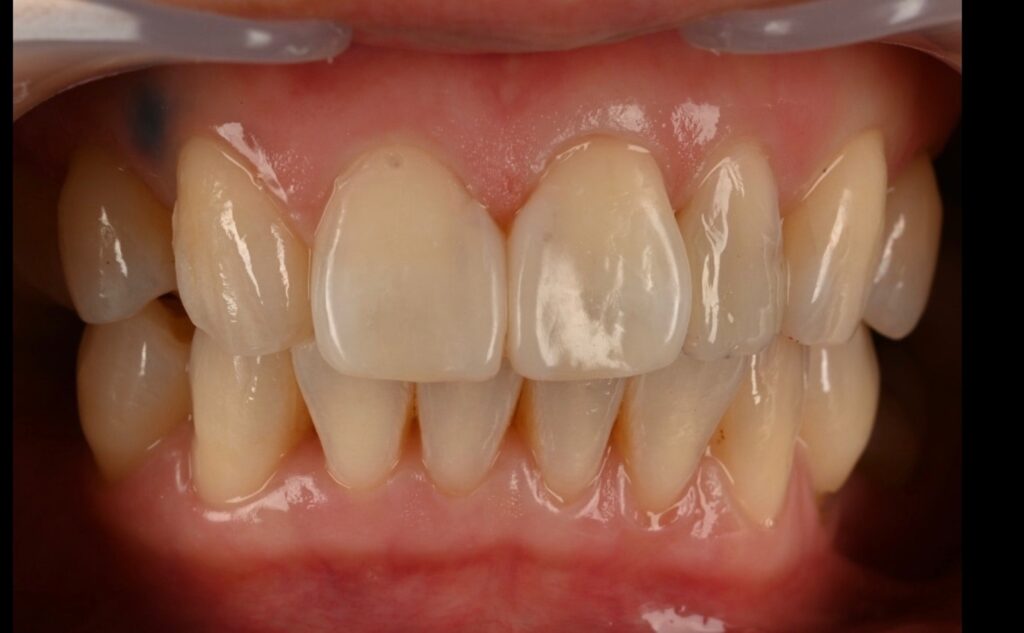

내원당일의 모습

레진 치아성형은 치료 당일은

1.색상이 발현되지 않아서 달라보일 수 있습니다

2.잇몸이 차오르는 모습을 봐야 합니다

-2주 후 기다려서 추후 경과를 봅니다-

2주후 모습입니다

색상과 그리고 잇몸이 차오른걸 볼 수 있습니다

최종 모습입니다

혹시 이상하다고 생각하시는 분들이 있겠지만

측절치 즉 왜소치의 레진성형도 완성이 되어서

치료 후의 모습이라고 보시면 됩니다